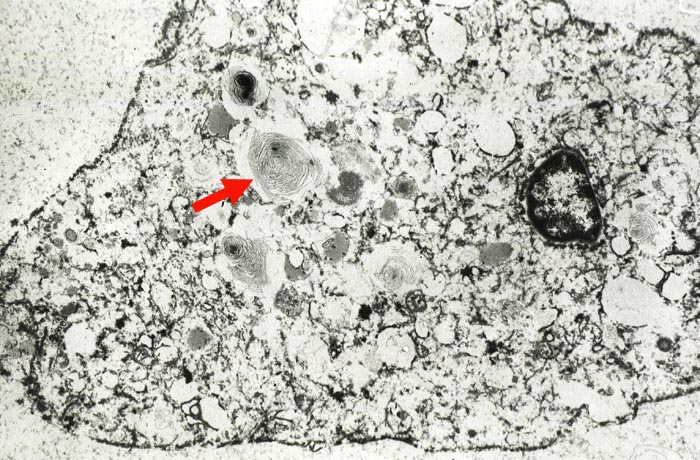

Myelinartige Einschlüsse in Pneumozyten II nach Amiodarone

Im Zytoplasma des Pneumozyten zahlreiche konzentrisch geschichtete an Myelin erinnernde Einschlüsse.

7000x

Die Myelinkörperchen beweisen, dass der Patient Amiodarone eingenommen hat.